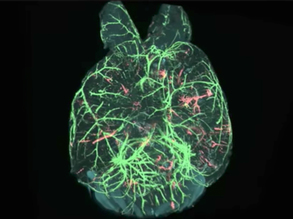

Clearly Brainy